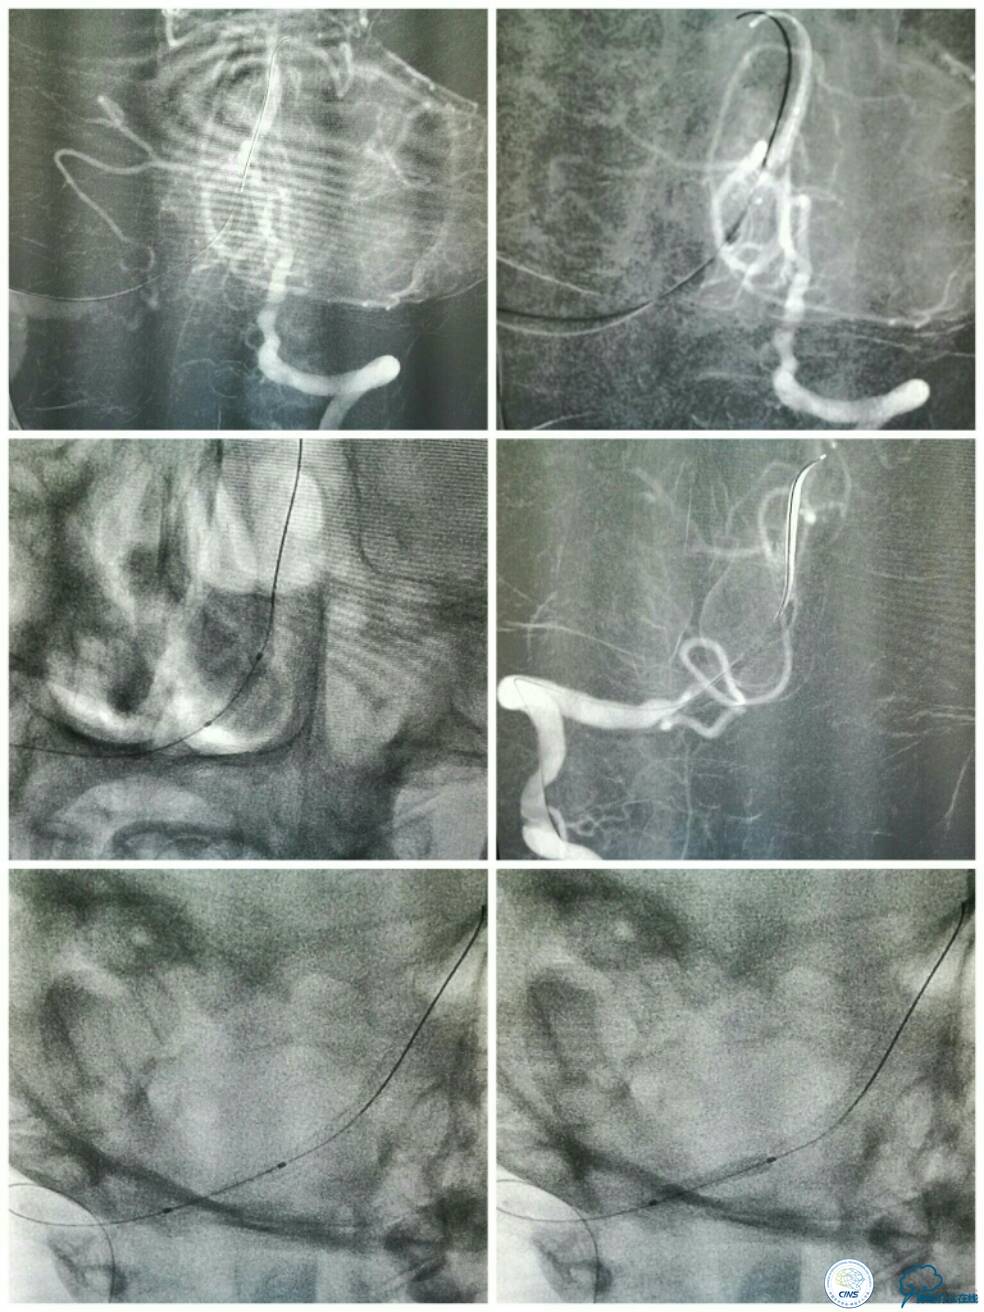

男性,61岁。主因眩晕、视物不清伴饮水呛咳1月入院。

病后就诊当地医院,予以双抗+积极控制危险因素治疗,但症状持续无缓解,就诊期间核磁检查提示右延髓新近脑梗死,MRA示双椎及基底动脉显示欠佳(图1)。

同期行DSA提示右椎动脉V4段发出右PICA后未见顺行显影(图2),左椎动脉V4段-基底动脉汇合处重度狭窄(图3),前循环向后循环的未见明显代偿(图4)。

血栓弹力图检查:AA抑制率98.2%、ADP抑制率47.7%。颅内CTA及后循环CT灌注检查提示:右椎动脉V4段未见显影,左椎动脉与基底动脉汇合处重度狭窄,右椎动脉V4段在汇合点以下有显影(图5);双侧小脑半球低灌注,右侧为著(图6)。

椎基底动脉高分辨核磁提示右椎动脉V4段闭塞,闭塞段管腔内可见高信号(箭头),考虑血栓,左椎动脉V4段至基底汇合处见向心性斑块(三角)(图7)。